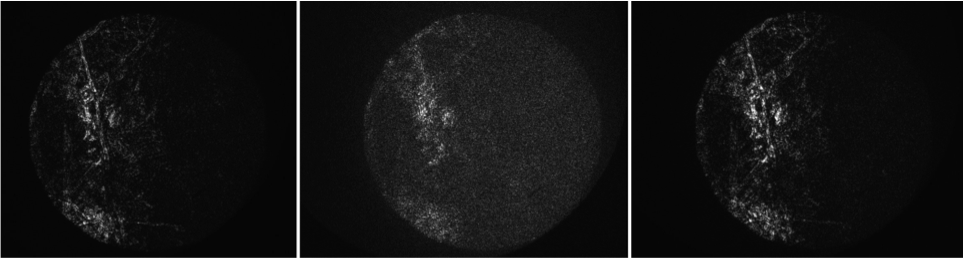

Des images de rétines explantées de rat, entre lame et lamelle, ont été obtenues sur le banc d’OCT plein champ seule. Après acquisition d’une pile d’images en-face (en XY), n’importe quelle coupe axiale (XZ ou YZ) peut être extraite des données.

Des images OCT de rétines de porc ex vivo ont été obtenues. On observe différentes couches.